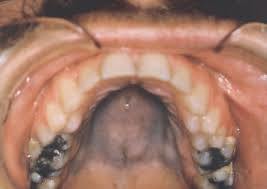

“Teeth floating in air” + skin plantar/palmar hyperkeratosis

Papilon-Lefevre syndrome